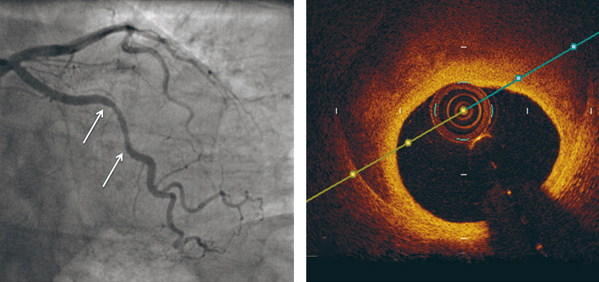

Forandringene kan bli mistolket som aterosklerose på angiografisk undersøkelse, spesielt hvis klassisk dobbeltlumenkontrastavfarging i arterieveggen mangler (3, 7, 8). Er man da i tvil om diagnosen hos en klassisk pasient, for eksempel en yngre kvinne uten risikofaktorer, kan man supplere med intrakoronar diagnostikk, som optisk koherens-tomografi (optical coherence tomography, OCT) og/eller intravaskulær ultralyd (IVUS) i tillegg til konvensjonell koronarangiografi (8).

Type 3 er ateroskleroseimitatoren, på grunn av angiografisk utseende som fokal og tubulær stenose. Den krever optisk koherens-tomografi eller intravaskulær ultralydundersøkelse for å kunne stille riktig diagnose. Denne siste typen representerte 3,9 % av studiepasientene (5, 9) (fig 1).